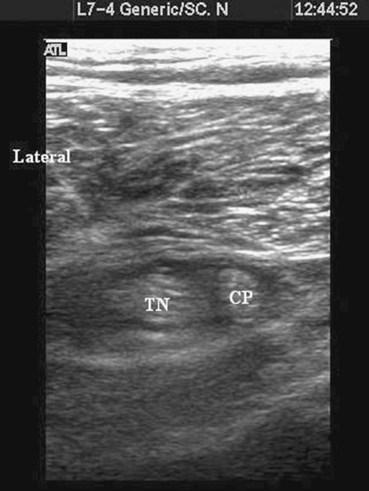

Figure 41-6. Local anesthetic (dark area)

seen encircling the two tibial and common peroneal nerves below the division of the sciatic nerve. TN, tibial nerve; CP, common peroneal. |